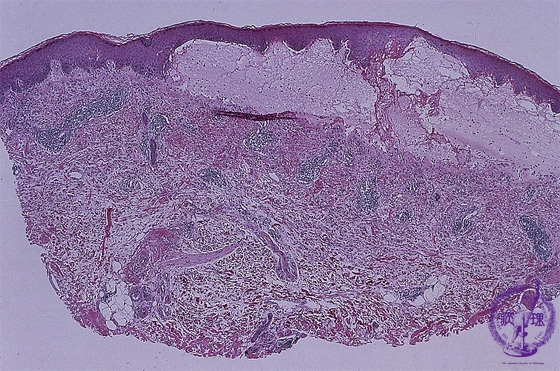

- ★(2)Vesiculobullous disease (Pemphigus vulgaris)

Microscopic image (Bullous pemphigoid): Subepidermal separation corresponds to the bullae. Biopsy taken from the edge of the bullae clearly shows the separation